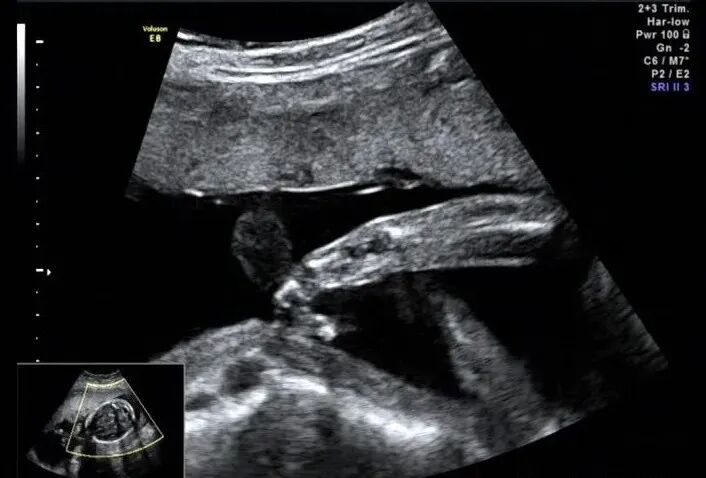

手指横断面仅显示两个,指间隙明显增大,裂隙深

再看脚也不对劲,马上启动三维超声,下图是三维超声表现

手脚都有问题,呈龙虾爪样,非常典型的手裂足裂,胎儿父母没有啥疾病